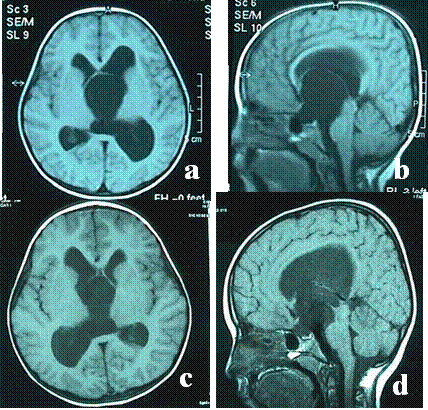

Resim 6: (a) ve

(b) yatay ve dikey düzlemlerdeki MRG görüntülerinde üçüncü karıncığı dolduran ve yan karıncıkların genişlemesine neden olan suprasellar araknoid kistin ameliyat öncesi görüntüleri,

(c) ve

(d) endoskopik ameliyat sonrası kistin küçüldüğü ve yan karıncıklardaki genişlemenin azaldığı izlenmektedir.